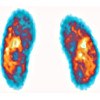

Статическая сцинтиграфия почек ребенку

Статическая сцинтиграфия почек позволяет оценить анатомо-топографический и функциональный статус почек путем регистрации поглощения радиофармацевтических препаратов (RFP) почечной паренхимы. Сканирование полипоза почечной области проводят в сцинтилляционной камере через 2-3 часа после введения нефротропного радиоизотопного соединения. В то же время оцениваются топография, форма, размер почек, угол поворота, характеристики накопления и распределения радиофармпрепарата. Показаниями к проведению статической сцинтиграфии почек в детской урологии являются аномалии развития и положения почек, пиелонефрит, мочеточниковый рефлюкс, ювенильная гипертензия и.